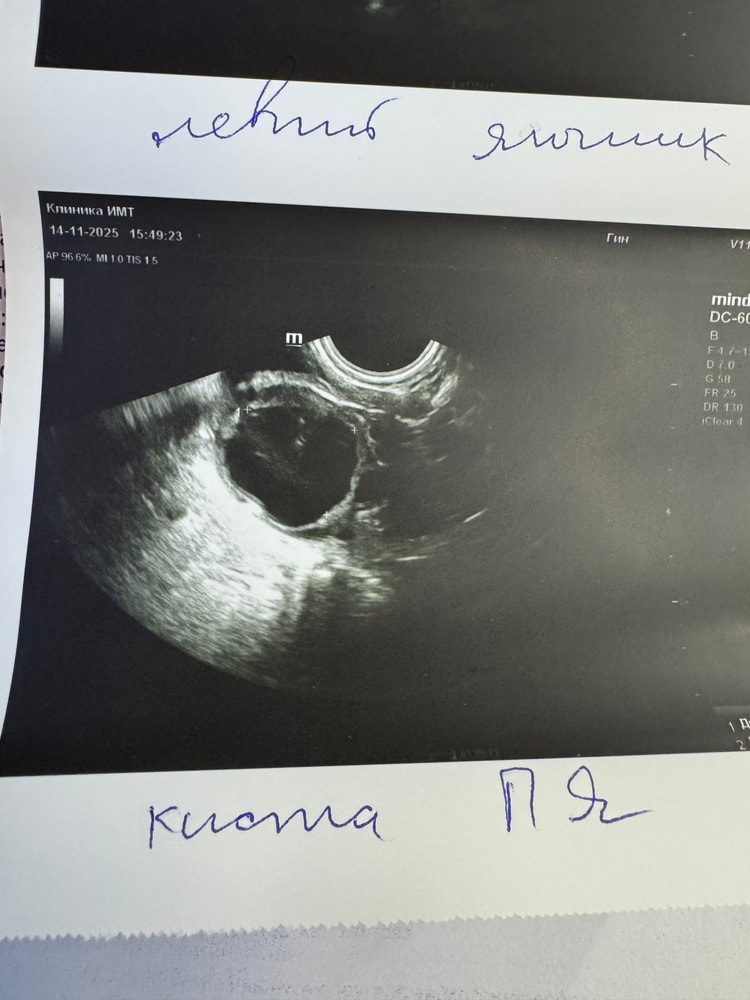

УЗИДевочки, подскажите, пожалуйста, есть ли надежда. Сделала узи на 22дц. На 17дц тест на овуляцию был явно положительным, субъективно овуляция произошла вечером того же дня (знаю, что по-хорошему через сутки-двое). Однако сейчас по узи жидкости в подзаматочном пространстве нет (но вроде могла уже рассосаться), ЖТ тоже никак не описано. Но нашли функциональную кисту в яичнике. Думаю: все, овульки не было, пролет. Однако я её чувствовала + был характерный ЯБ. Очень смутило, что врач узи не проверила кровоток у образования - просто быстро посмотрела и сказала, что киста.. Разбирающееся, подскажите, данное образование хоть как-то может смахивать на ЖТ? Или надежды нет?) Читала у некоторых, что путали ЖТ с фолликулярной кистой.

Добавляю: проконсультировалась с другим врачом, сказал, что очень похоже на ЖТ и овуляция, вероятно, все таки была. Надеюсь 🙏🏻🥹